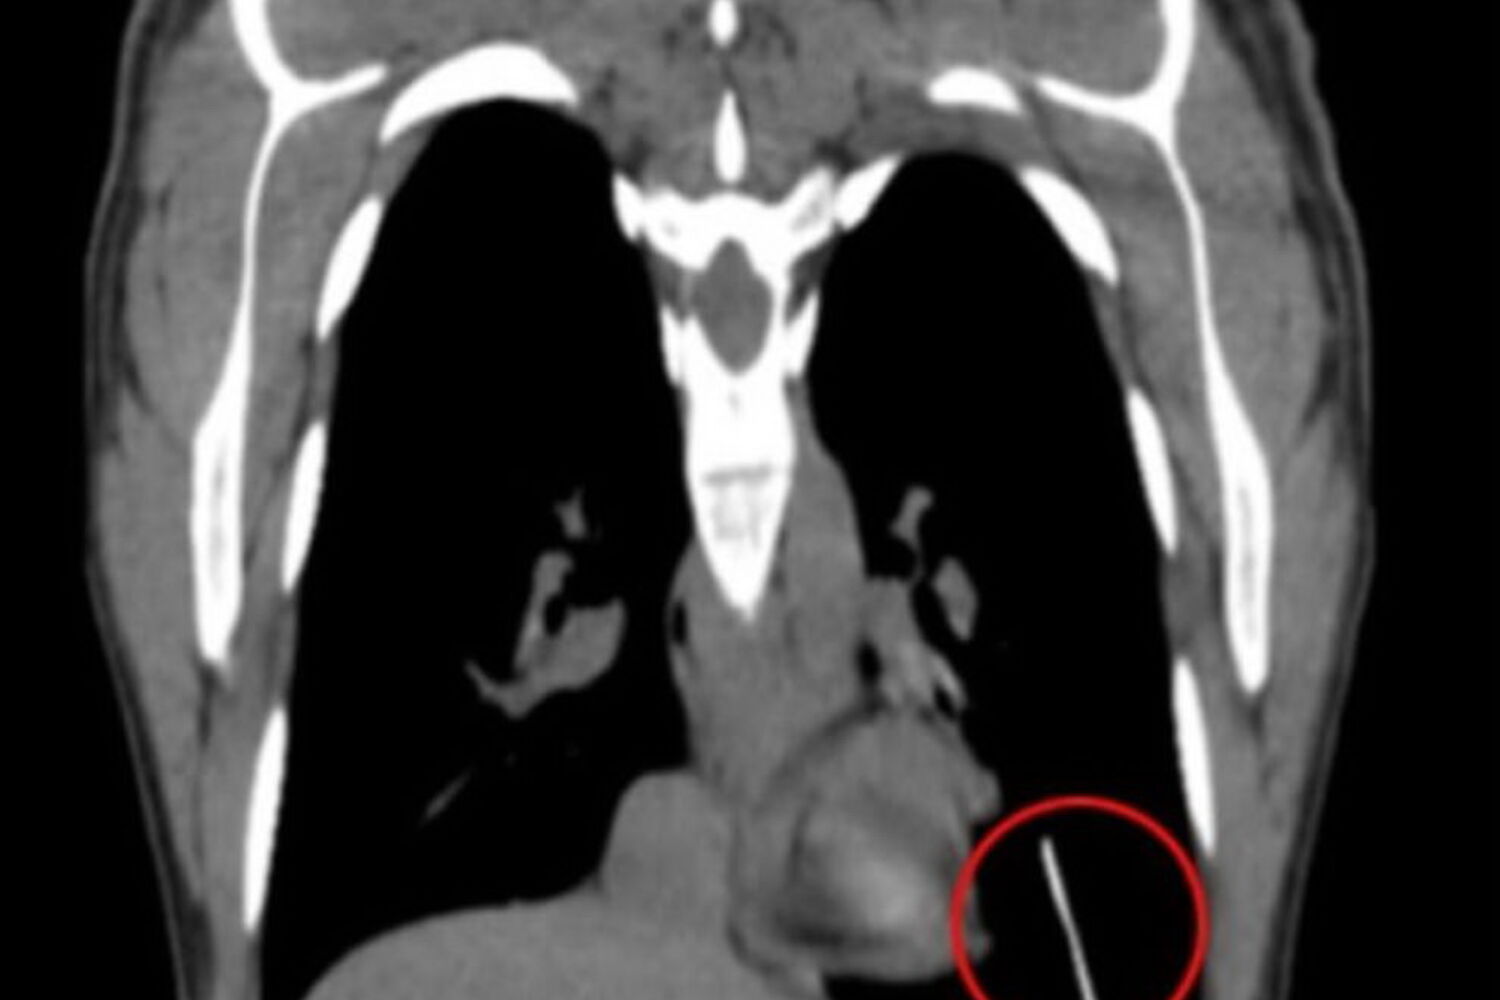

Exames posteriores mostraram que o implante estava instalado no fundo do pulmão esquerdo. No relatório médico, os profissionais sugeriram que o dispositivo tenha migrado para o pulmão através de um vaso sanguíneo, ao ter sido colocado muito profundamente. Outra das hipóteses colocadas foi a prática de exercicío fisíco intenso logo após a colocação, o que pode aumentar o risco de migração vascular.